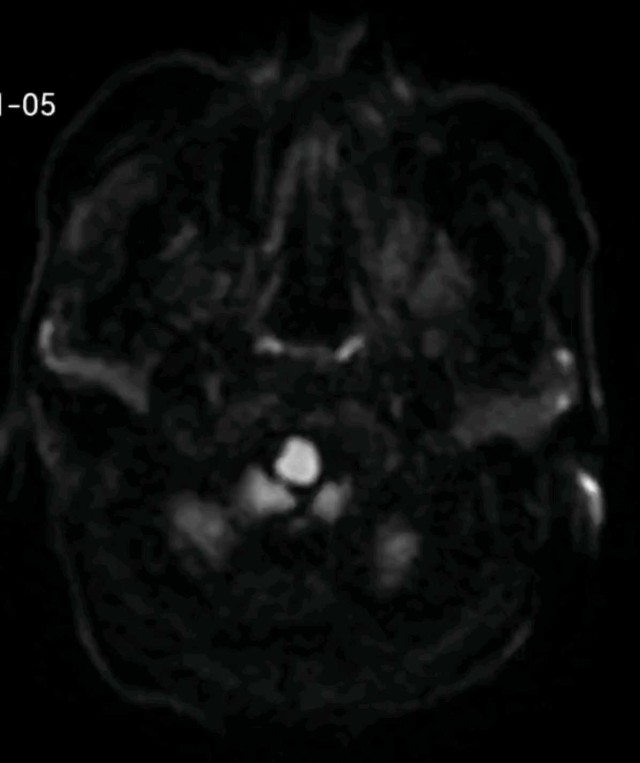

反思 | 赶高铁时一过性晕厥的老年男性

昨天值班遇到的一例晕厥病例,差点漏诊,而最终的解法,始于最简单而质朴的查体。国庆中秋双节的最后一天,8号的早上8点,抢救室床旁晨交班,病人依旧是多而重,交到6床,一个刚入室不久的病人,准备去做CT,夜班医师汇报病史:69岁男性,本次因“头晕伴一过性晕厥1小时”为主诉入抢,1小时前于高铁站因即将赶不上高铁走路快时突发头晕,伴一过性晕厥,约3-4分钟后清醒,清醒后诉今晨未吃早餐,已服用降压药物,仍有头晕头痛、四肢乏力等不适,无胸闷胸痛,无畏寒发热,无咳嗽咳痰,无恶心呕吐,无肢体麻木,无视物模糊等不适,路人拨打120送至我院急诊就诊。既往高血压,长期服用氨氯地平+福辛普利,血压控制一般;糖尿病,长期